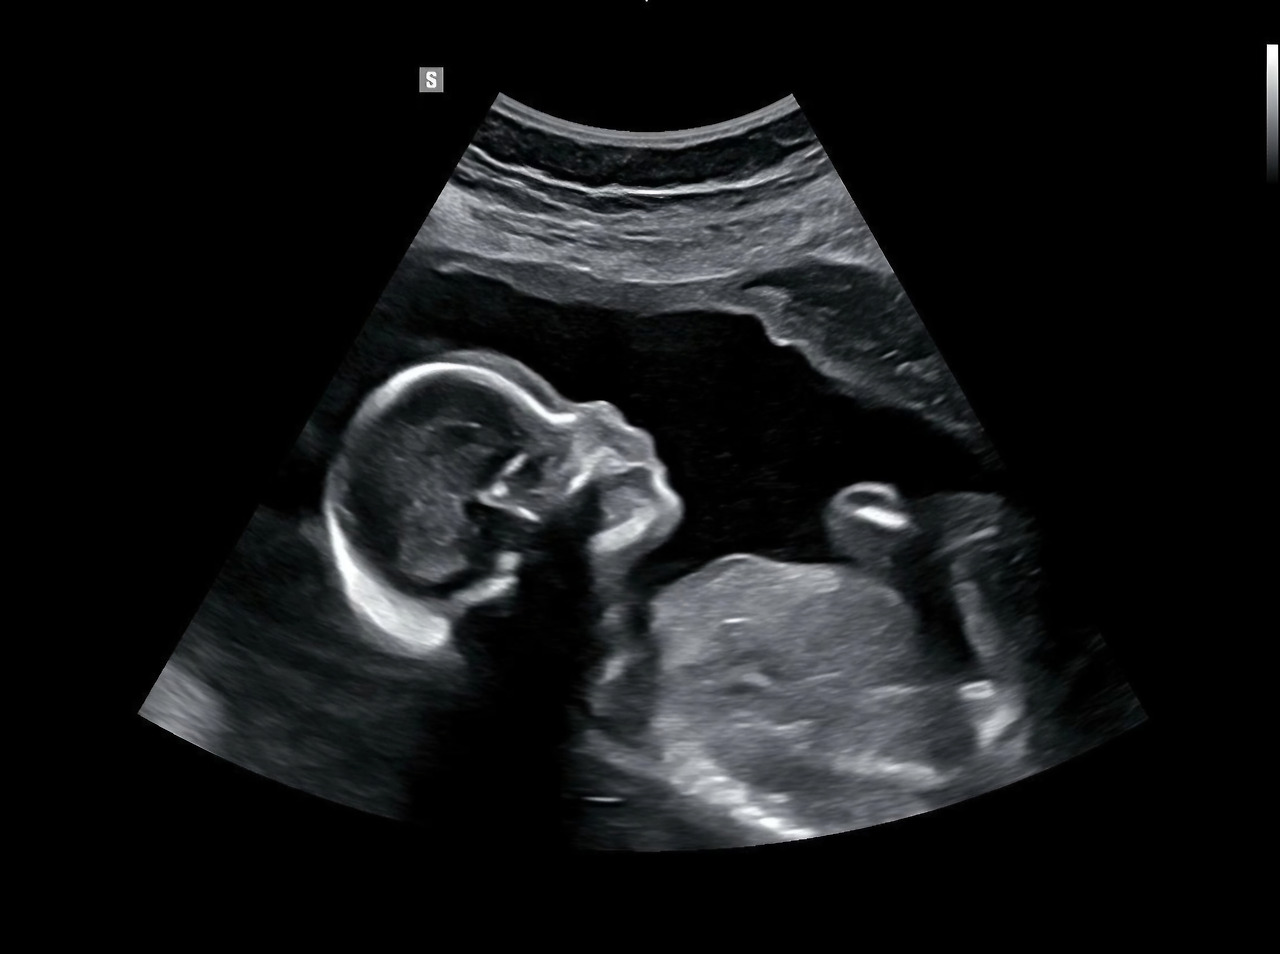

25년 11월 17일 정밀초음파.

그저께는 한 달 만에 병원에 가서 대망의 정밀 초음파를 봤어.

말 그대로 링링의 머리부터 발끝까지 정밀하게 살펴보는 거야.

링링의 뇌부터 손가락, 발가락, 콩팥, 심장 등등을 하나하나 확인하는 데만 거의 20분이 걸렸어.

네가 발 한쪽을 쉽게 보여주지 않아서 선생님이 조금 애를 먹었지.

9mm 아기집에 점처럼 붙어있던 링링은 어느새 20cm 넘게 커 있더라.